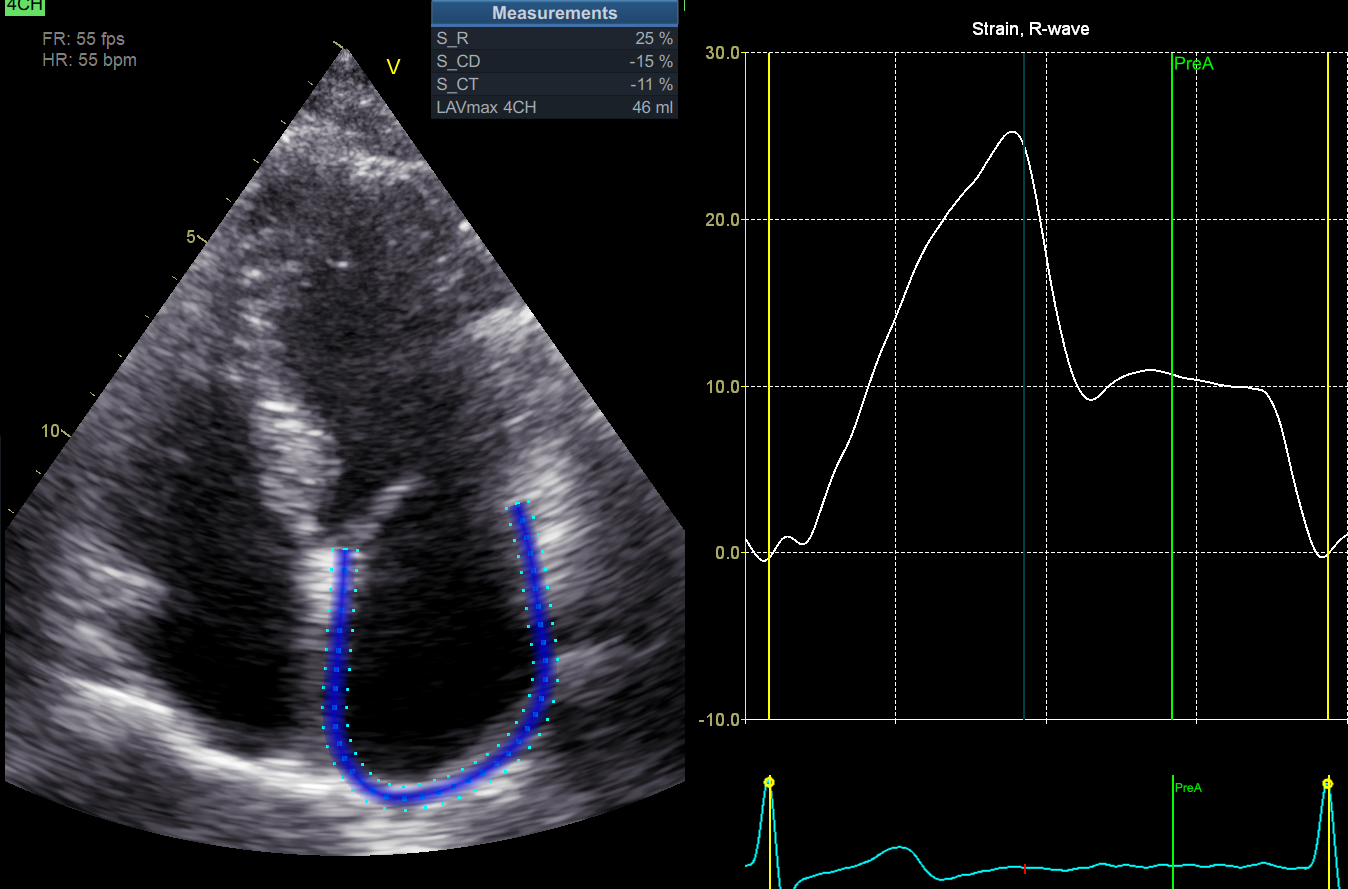

We evaluated GLS that is transmural strain. Myocardial wall is composed of 3 myocardial layers, endocardium, epicardium and mid-layer and strain can be calculated in each of them [1], that may provide further insights into post-COVID complications. Which layer is responsible for decrease of GLS in post-COVID patients? In which myocardial layer myocytes are more vulnerable regarding the binding by viral particles? As we can see at Figure 1, endocardial strain is the highest and the epicardial strain is the lowest.

Figure 1. Strain in 3 myocardial layers in patient with post-COVID syndrome. Apical 4-chamber view.

1. Endocardial strain.

2. Mid-layer strain

3. Epicardial strain.